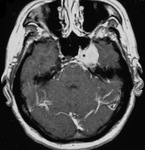

Meningioma: imagem coronal aumentada com contraste demonstra meningioma no seio cavernoso no lado esquerdo

Da coleção pessoal de William T. Couldwell; usada com permissão